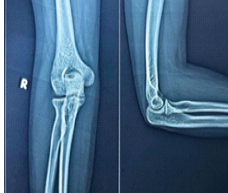

Management of a Post-traumatic Stiff Elbow: A Case Report

Parin Shah , Priti Ranjan Sinha , Shubham Jain , Dhairya Shah , Ayush Sharma , Nikhil Singh

………………………………p.189-197